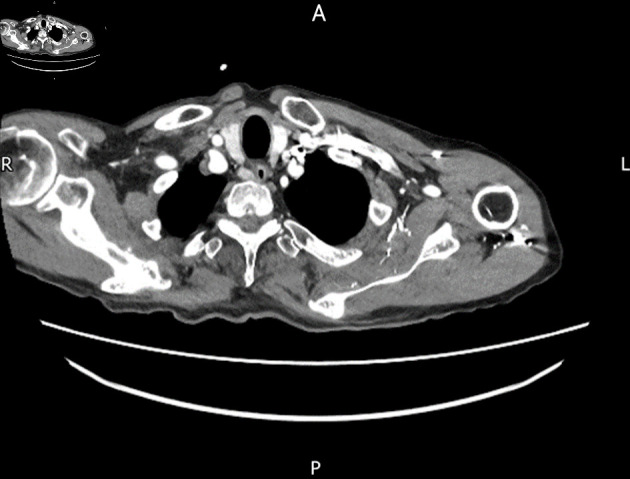

Abstract Image